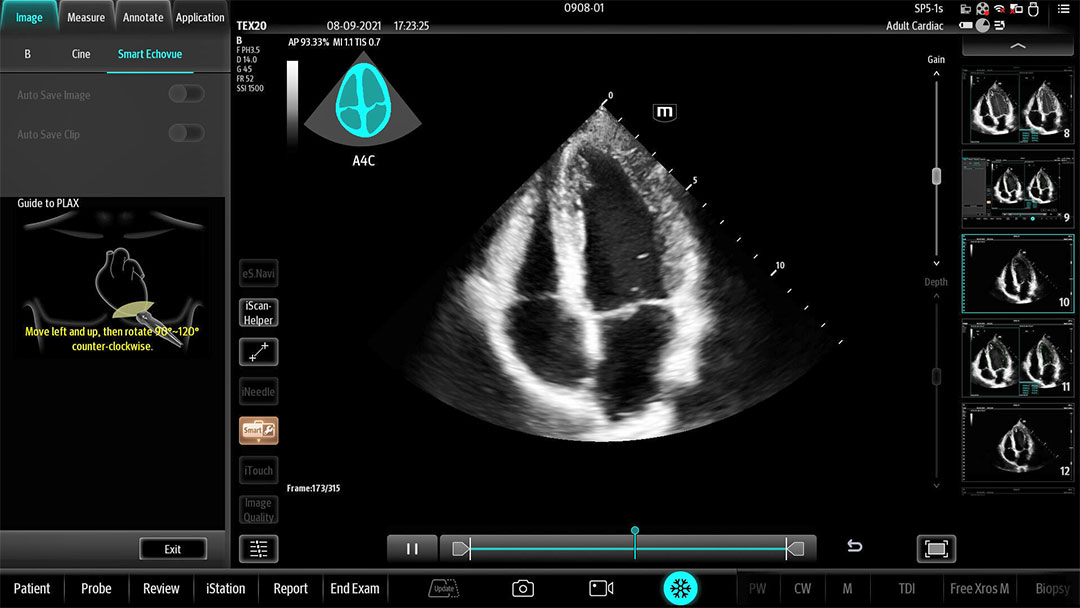

The technology-rich TE X Ultrasound System gives clinicians access to market-leading artificial intelligence (AI)-powered Smart Tools, an ergonomically designed system, and proprietary software-based beamformer Zone Sonography Technology+ (ZST+). By incorporating these elements, the TE X Ultrasound System provides access to advanced diagnostic data, the ability to adapt to the various clinical scenarios at point of care, and best-in-class imaging to help them provide a higher standard of care.